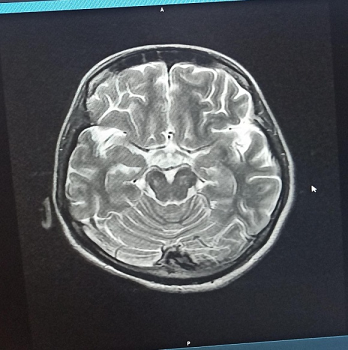

Radiological Findings:  Figure 1 : Brain MRI (T2-weighted axial view) showing hyperintensities in the posterior medulla, suggestive of NMOSD involvement.

Nevertheless, the disease’s progression extended beyond peripheral manifestations. An MRI of the brain revealed T2 hyperintense areas in the posterior medulla—atypical for GBS—and serological analysis confirmed MOG antibody positivity, identifying “Neuromyelitis Optica Spectrum Disorder” (NMOSD) as a concurrent condition. The combination of central and peripheral demyelination, although rare, has been increasingly acknowledged, particularly among cases positive for MOG antibodies [12–15]. MOG-associated NMOSD commonly presents with optic neuritis or transverse myelitis, but brainstem lesions, particularly in the medulla, have also been documented. Symptoms like dysphagia, vertigo, and hiccups indicate such involvement, corresponding with this patient’s clinical presentation. Therefore, it was crucial to determine whether the decline was attributable to peripheral GBS or central NMOSD. The patient’s situation was further complicated by severe illness and a secondary hospital-acquired infection. A chest X-ray indicated bilateral opacities, and cultures identified multidrug-resistant Acinetobacter baumannii, a pathogen known for its resistance and association with ICU settings [12][16][17]. Effectively addressing these infections necessitates careful antibiotic selection and stringent infection control measures. Remarkably, despite the simultaneous pathologies and infection, the patient demonstrated improvement with supportive care alone—ventilatory support, nutrition, physiotherapy, and appropriate antibiotics. She did not need immunotherapy options such as IVIG, plasmapheresis, or corticosteroids, which are generally considered for GBS and NMOSD. This outcome emphasizes that tailored care, based on clinical stability and gradual improvement, can, in certain cases, be sufficient without aggressive treatment[18][19]. From a broader perspective, this case highlights that central and peripheral demyelinating conditions can coexist. Disorders associated with MOG may affect both areas, increasing the need for awareness of atypical manifestations. Furthermore, it underscores the significance of multidisciplinary cooperation—neurology, critical care, infectious disease, physiotherapy, and nursing teams all played vital roles in the recovery process.[20-23] In summary, this report emphasizes the importance of promptly identifying overlapping neuroimmunological disorders, conducting thorough diagnostic assessments, and exercising careful clinical judgment in customizing treatment. |